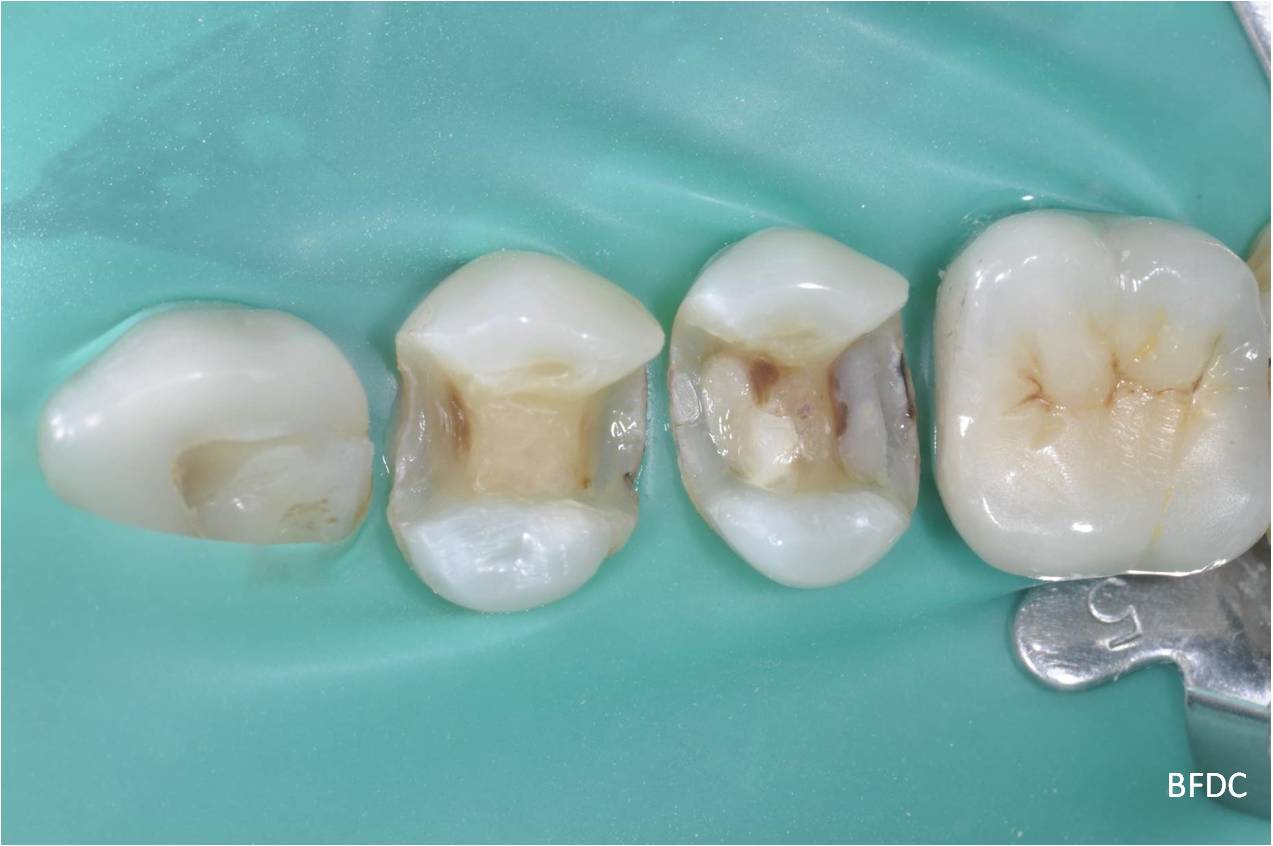

崁體修形